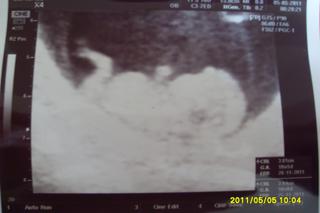

@mirkatv tak toto nie je ziadna cysta toto je tehu 🙂 gratulujeeeeeeeeeeeeeem 🙂

Holky, tak jsem zpět, dr. je úžasný, všechno vysvětlil, na utz vše ukázal včetně žloutkového váčku, popisoval amniový vak.. Miminko kopalo, protahovalo se 🙂, srdíčko bylo první co jsem na monitoru hledala - tlouklo krásně. Odpovídáme velikostí 10+5 tt, pak měřil znovu a možná i 10+6 tt. Poprvé v životě mi někdo měřil pánev, no péče úplně jiná, než jsem znala doposud, jsem ráda, že jsem přešla..

Fotečka sice nic moc, ale snad tam něco uvidíte, pan dr. se omlouval, že je to tak světlé, ale já jsem spokojená 🙂.

@daisyna moooc gratulujeeeeeeeem 🙂 fotecka ja kraasna miminko sa ma k svetu a je krasne cakat sa oplatilo 😉 🙂

@mirkatv tak to bude najskor tehu🙂 gratulka z celeho srdcA